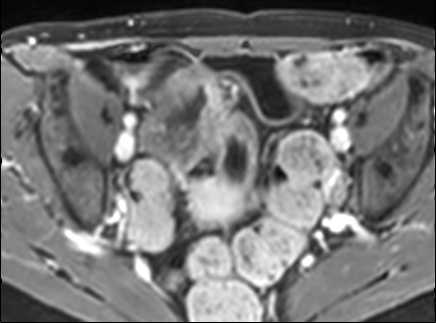

Bệnh nhân nữ 48 tuổi, đang điều trị bằng thuốc kháng TNF, được chỉ định nội soi đại tràng.

Phát hiện hẹp lòng ruột ở đại tràng sigma, không thể vượt qua được khi nội soi.

MR-enterography được thực hiện để đánh giá mức độ lan rộng của chỗ hẹp.

Cuộn qua các hình ảnh.

Ruột non bình thường, nhưng ghi nhận các đoạn hẹp ở đại tràng xuống và đại tràng ngang.

Cả hai đoạn hẹp đều có thành ruột dày đến 8 mm và ngấm thuốc rõ rệt theo kiểu niêm mạc ở đại tràng xuống và kiểu phân lớp ở đại tràng ngang.

Giãn ruột trước chỗ hẹp được ghi nhận ở cả hai đoạn.

Do các chỗ hẹp này không hiện diện khi nội soi đại tràng trước khi điều trị kháng TNF, nhiều khả năng chúng đã hình thành trong quá trình điều trị.

Do đó, quyết định phẫu thuật cắt đại tràng gần toàn bộ với miệng nối hồi-sigma đã được đưa ra.